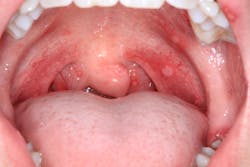

A healthy 16-year-old male presented with this chief complaint: I got my wisdom teeth out five days ago, and I can’t eat or swallow; it hurts. I have bumps all over in my mouth.

Clinical assessment revealed multiple white lesions with red borders salt-and-peppered in a generalized fashion throughout the entire oral cavity. The gum tissues were swollen and any light palpation/touching of the lesions resulted in bleeding and pain. See clinical photos below.

Acute herpetic gingivostomatitis